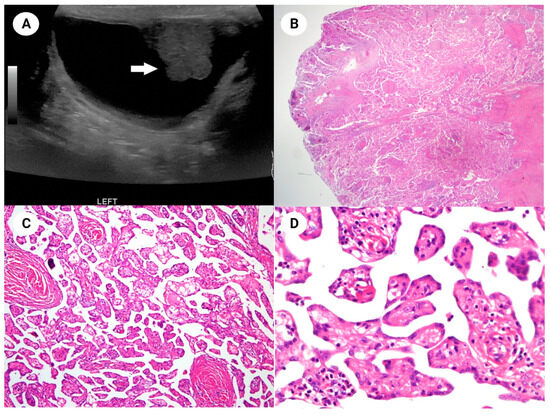

Well-Differentiated Papillary Mesothelial Tumor of the Scrotum with Suspicious Invasion

Im, S.; Yoo, J.M.; Cho, U. Well-Differentiated Papillary Mesothelial Tumor of the Scrotum with Suspicious Invasion. Diagnostics 2024, 14, 169. https://doi.org/10.3390/diagnostics14020169